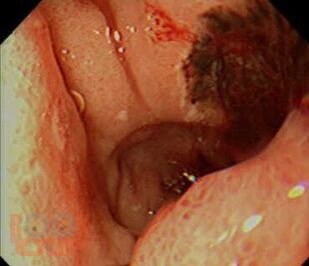

Вторая части учебного пособия «Осложнения язвенной болезни желудка и двенадцатиперстной кишки» посвящена язвенным желудочно- кишечным кровотечениям. В настоящем пособии освещены вопросы этиологии и патогенеза острых желудочно-кишечных кровотечений, их классификация, клиническая картина, современные методы диагностики. Подробно изложены принципы консервативного, эндоскопического и хирургического лечения данной патологии.